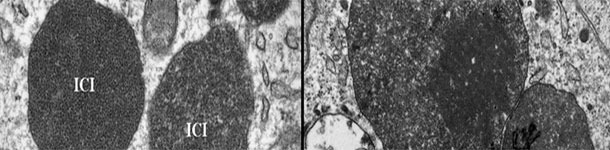

Microscopía electrónica de un linfonodo de un cerdo con PCV2-ES. Nótese la presencia de cuerpos de inclusión intracitoplasmáticos de PCV2 (CII); en algunas zonas, las partículas virales pueden disponerse en estructuras paracristalinas (recuadro de la imagen derecha). Foto cortesía de Carolina Rodríguez-Cariño, tesis doctoral.